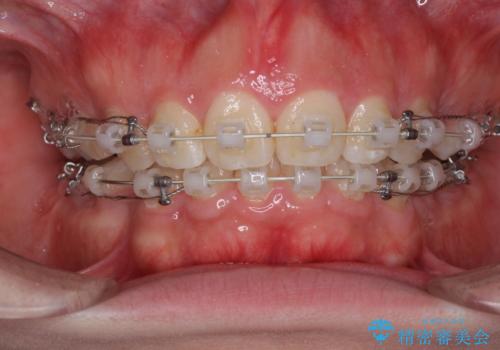

- 矯正装置

- 審美装置

- 治療計画

- 歯並びがガタガタなのと、口が閉じずらいのを主訴に来院されました。

上下左右の歯を1本ずつ、合計4本抜歯して、ワイヤー矯正を行うこととなりました。